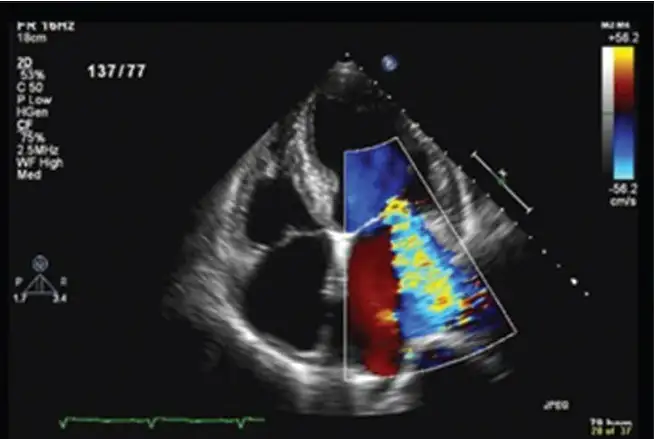

2015年,美国心脏协会修订了琼斯标准,纳入了新技术如多普勒超声心动图,以及对疾病流行病学的新认识。修订后的指南考虑了人群内的风险,提供了两条独立的诊断路径,优先考虑低风险人群的特异性和中高风险人群的敏感性。超声心动图现在被推荐用于所有疑似或确诊急性风湿热的患者,亚临床心脏炎可以在所有人群中满足急性风湿热的主要标准。

多普勒超声心动图在风湿热中的价值在于它能够检测亚临床心脏炎。由于心脏炎可能导致急性心力衰竭和慢性瓣膜病,它是急性风湿热中最严重的主要发现。临床心脏炎定义为与主动脉瓣或二尖瓣关闭不全一致的杂音。

多普勒超声心动图已被证明可以在我们耳朵听到杂音之前检测到这种瓣膜病变。这种现象被称为亚临床心脏炎。许多研究表明,急性风湿热患者中亚临床心脏炎的患病率相当高。一项2007年的荟萃分析包括来自五大洲的23项研究,表明急性风湿热患者亚临床心脏炎的加权汇总患病率为16.8%,其中44.7%的患者瓣膜受累随时间恶化。

超声心动图筛查的意义是深远的。一项研究表明,如果仅依赖临床诊断,大约90%的超声心动图检测到的病例会被漏诊。这些病例不能仅仅因为超声心动图筛查被认为太昂贵而被漏诊和不治疗,并面临风湿热复发的风险。需要更便宜的超声心动图筛查模式。也许,使用大学毕业生作为筛查人员太昂贵了。也许,了解心脏解剖学的高中毕业生可以被使用。这种模式将大大降低超声心动图筛查的成本。手持式心脏超声设备的价格已大幅下降。

急性风湿热和随之而来的风湿性心脏病在中低收入国家仍然极其常见,具有社会、经济和医学后果。在确诊为风湿性心脏病证据的儿童中进行基于每月青霉素注射的二级预防,已被证明是减少风湿性心脏病负担最有效和最具成本效益的策略。因此,早期检测对于减少风湿性心脏病的负担是必要的。